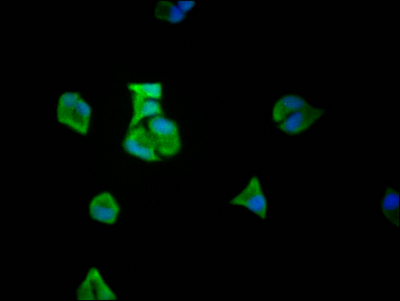

Immunofluorescence staining of Hela Cells with CSB-RA932542A0HU at 1:50, counter-stained with DAPI. The cells were fixed in 4% formaldehyde, permeated by 0.2% TritonX-100, and blocked in 10% normal Goat Serum. The cells were then incubated with the antibody overnight at 4℃. Nuclear DNA was labeled in blue with DAPI. The secondary antibody was FITC-conjugated AffiniPure Goat Anti-Rabbit IgG (H+L).